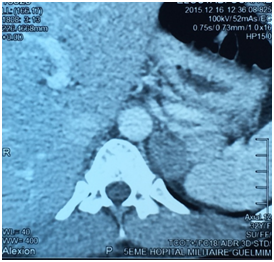

E.O. was a 31-year-old female, with a history of celiac disease under gluten-free diet, and a pregnancy-induced hypertension one year ago, without having been screened for secondary hypertension, to the best of our knowledge. A satisfactory blood pressure (BP) has been reached under treatment with nicardipine (100mg/day). The patient was admitted to our hospital because of headache, muscle weakness and heart palpitations, for two weeks. On physical examination, the patient was in regular general condition and with a healthy coloring. Her weight was 53.5 kg and height 162 cm (BMI=20.41Kg/m2). Blood pressure measured with a manual armlet 190/110 mmHg, heart rate 100beats/minute and regular, respiratory rate 18cycles/min, body temperature 36.9°C. On auscultation, her lungs were clear with no rales. Her heart auscultation showed regular cardiac rhythm with cardiac sounds of normal intensity and no murmurs. Her lower limbs showed symmetric palpable pulses and no edema. The power and sensation of both lower and upper limbs were normal. The abdominal examination showed hydro-aerial noise, no visceromegaly and no abdominal murmur. Thyroid gland examination was normal. There was neither obesity nor hirsutism. Other physical examination was normal. Laboratory findings were as follows: serum potassium 1.68mEq/L (normal range (NR)= 3.5-5.1), sodium 143 mEq/L (NR=136-145), alkaline reserve 32mEq/L(NR=22-31), corrected calcium 95mg/L(NR=86-100), phosphorus 29.9mg/L (NR=25-45), urea 0.15g/L (0.13-0.45), creatinine 3.9mg/L(NR=5-9). The complete blood count and coagulation indices were normal. The thyroid function test was normal (0.94mU/L; NR=0.27-4.2). The measurements of sodium and potassium in the 24-hour urine were 54mEq/L (NR=54-190) and 63 mq/L (NR=25-125), respectively. The ECG showed presence of changes of hypokalemia, U waves and no hypertension changes. Echocardiography assessment of hypertension was negative, and there was no hypertension retinopathy. She was treated with boluses of intravenous potassium chloride and oral potassium supplements, for 260 mmol/day over 6 days. Initially her hypertension was treated with intravenous nicardipine utilizing an electrical syringe pump. Despite intravenous and oral potassium supplementation, her serum potassium level remained low. The PA was suspected because of persistence hypokalemia in association with hypertension and alkalosis. However, after correction of serum potassium level, the patient was examined for the plasma aldosterone concentration (PAC) and direct rennin concentration (DRC). Results revealed a low DRC level of 0.9mUI/L (NR=2.8-39.9), along with a very high PAC level of 2613pmol/l (NR=83-405). The aldosterone to rennin ratio (ARR) was 523pmol/l per mUI/l (N<64). Subsequently, after a three-day oral sodium load, 24-hour urine was tested for the concentration of sodium (260mmols) and aldosterone (27.3mg). Abdominal computerized tomography (CT) revealed a 28x21 mm hypo-dense mass (1UH of density), not enhanced by the contrast product, over the left adrenal gland (Figures 1) (Figures 2). After using spironolactone 100 mg/day and nicardipine 150 mg/day for one month preoperatively, the BP normalized (BP=125/85 mmHg), the headache, weakness and heart palpitations significantly improved, and the serum level of potassium was 4.5 mEq/L. Therefore, the patient underwent a successful laparoscopic left adrenalectomy (Figure 3), and the postoperative course was well. The macroscopic tumor consisted of an ovoid piece of yellow color tissue with weight: 28gr, circumscribed mass: 20x30mm in dimensions adjacent to adrenal tissue. Histologically, the adrenal mass showed an encapsulated epithelial neoplasia with cells of clear cytoplasm, round nuclei and conspicuous nucleoli. However, necrosis, capsular invasion and atypical mitosis were not found (Figure 4). The anatomic pathological diagnosis was adenoma of the adrenal gland consistent with Conn’s adenoma. The patient was normotensive and serum potassium was 4.5mEq/L without any antihypertensive medication or supplement for the last three months after discharge. She was stable with a optimal control of blood pressure without hypokalemia with a 2-year follow-up.